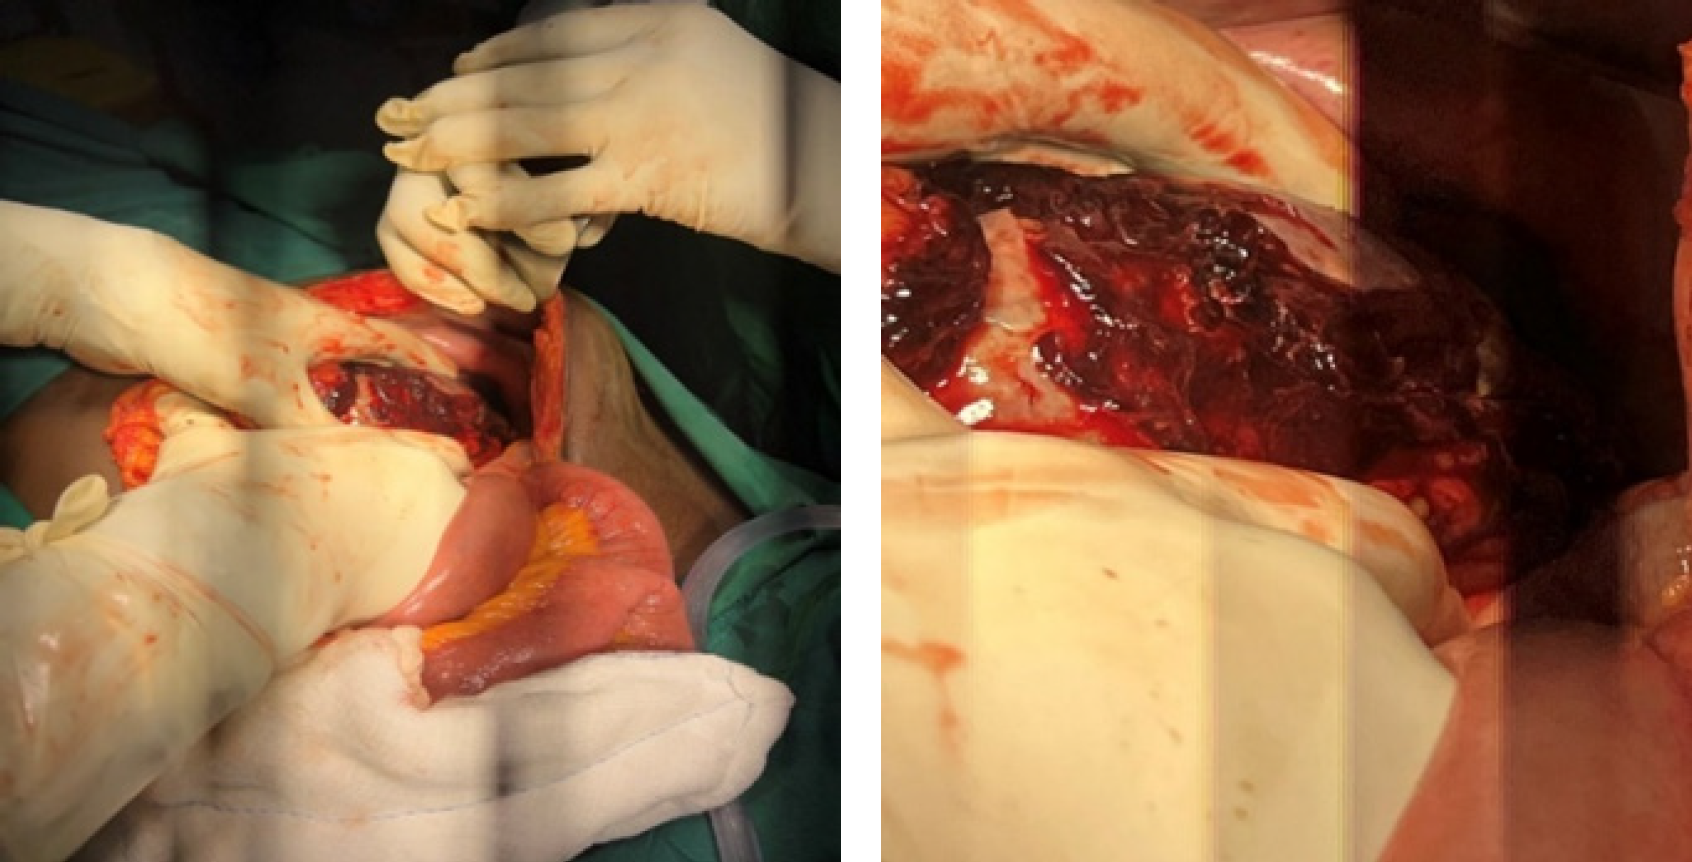

Case: A 55-year-old male involved in a motor vehicle accident presented to our facility hemodynamically stable, seven days after initial management for a traumatic hemothorax, with a missed diagnosis of diaphragmatic rupture and herniated, shattered spleen. The diagnosis was confirmed following a thorough physical examination and cross-sectional imaging. Laparotomy was conducted to perform a splenectomy and repair a diaphragmatic rupture, and the patient had an uneventful postoperative recovery.